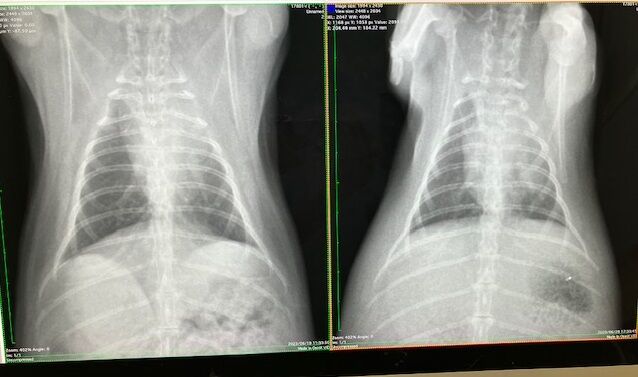

胸の方は

こちらも大きな問題なさそう、ですが、

心臓の輪郭がはっきりしてない箇所があります。

(向かって右上、白くモヤってるところ)

去勢手術の術前検査で撮影したレントゲンがあったので比較すると、

ほとんど変化がありません。

(向かって左が現在)

なので、リンパ腫などの可能性は低く、肺の一部が弱ってる(しぼんでる?)のかなと。

(うさぎは肺が6個やったっけか?

1つ2つ機能しなくなっても生活に支障はない、とか…

過去の記憶ですが💦)

また、生まれつき(先天性)かも。

※緊急性の高い呼吸困難の症状が出ていない場合での見解です※